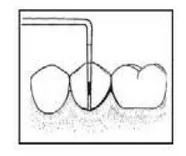

Instrumentem przedstawionym na ilustracji stosowanym w chirurgii stomatologicznej jest